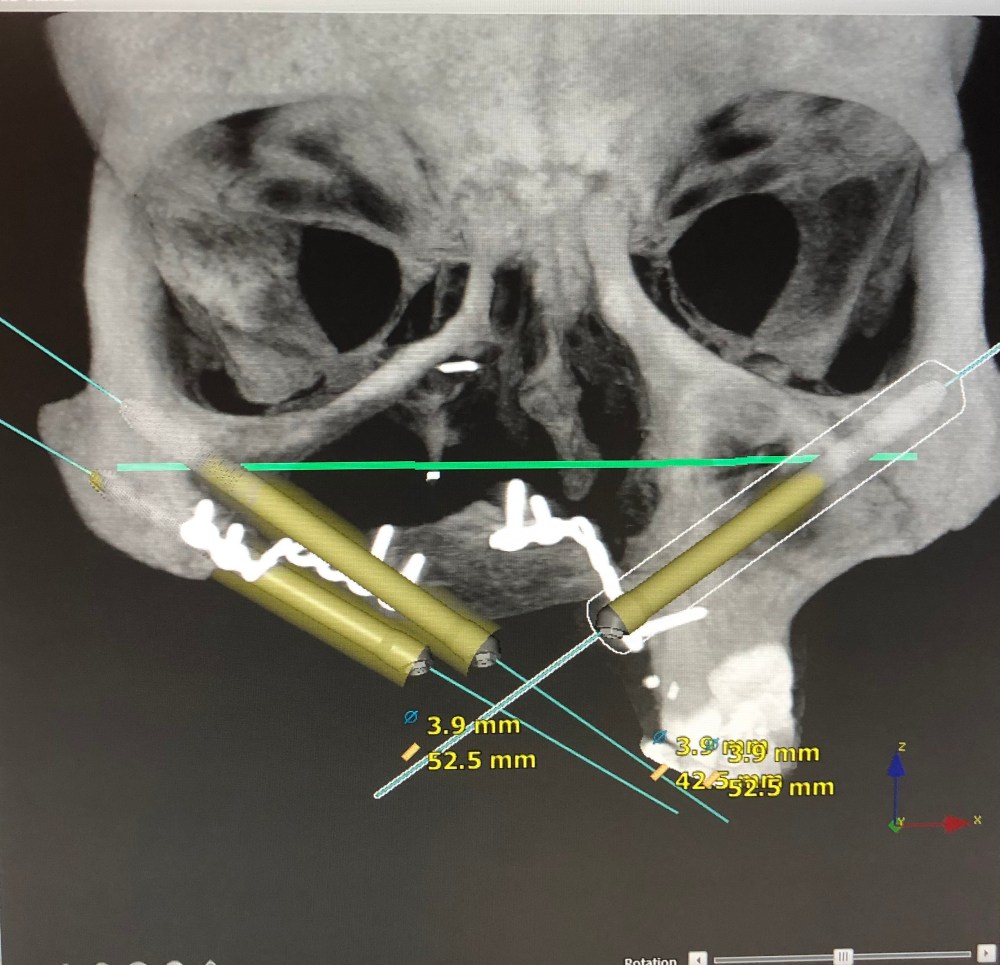

And these were the plans for implants – they are called zygomatic implants, and we wanted three through the roof of my mouth and into my cheekbones:

So we went in to the surgery with these plans and models, and a ‘best case scenario’ but of course going in to surgery (or at least one this difficult), you never actually know what is going to happen.